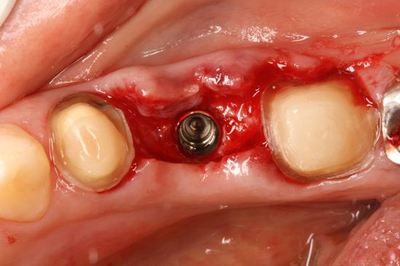

ここからは粘膜を剥離して実際の歯槽骨を見ながらドリリングします。

ドリルのサイズをステップアップして最終サイズまで拡大しました。

インプラント埋入前にタップを切ります。

インプラントは私が信頼するストローマンインプラント(スイス製)です。

ボーンレベルインプラント Φ4.1mm 8mm です。

インプラントの埋入を終えました。